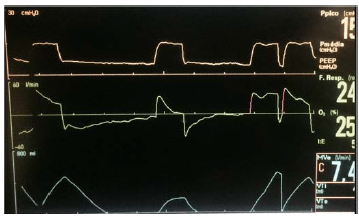

Uma paciente de 58 anos de idade encontra-se mantido em ventilação mecânica invasiva. As curvas do ventilador são as demonstradas na imagem apresentada.

Qual a assincronia demonstrada?

Assinale a alternativa que indica a ciclagem nesse ajuste de ventilação.

Qual o modo ventilatório?

A variável limite dessa ventilação é